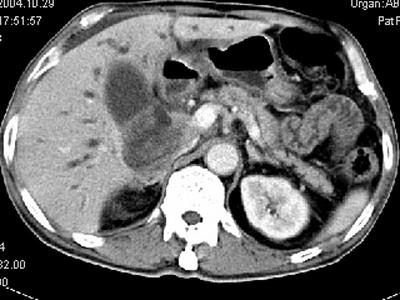

问题 男,58岁,患者右季肋区疼痛,皮肤黄染,可触及肿大胆囊,B超提示胆囊颈部肿块影,CT所见如图,最可能的诊断是 ( )

选项 A、慢性胆囊炎 B、胆囊腺肌增生症 C、胆囊癌 D、胆囊黄色肉芽肿 E、胆囊息肉

答案 C